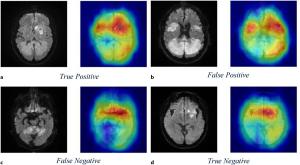

(Source: Karger Publishers) This visualization supports our hypothesis that the machine learning algorithm can differentiate a stroke due to AF or LAA based on the patterns and features of the infarct regions.

(Source: Karger Publishers) This visualization supports our hypothesis that the machine learning algorithm can differentiate a stroke due to AF or LAA based on the patterns and features of the infarct regions.